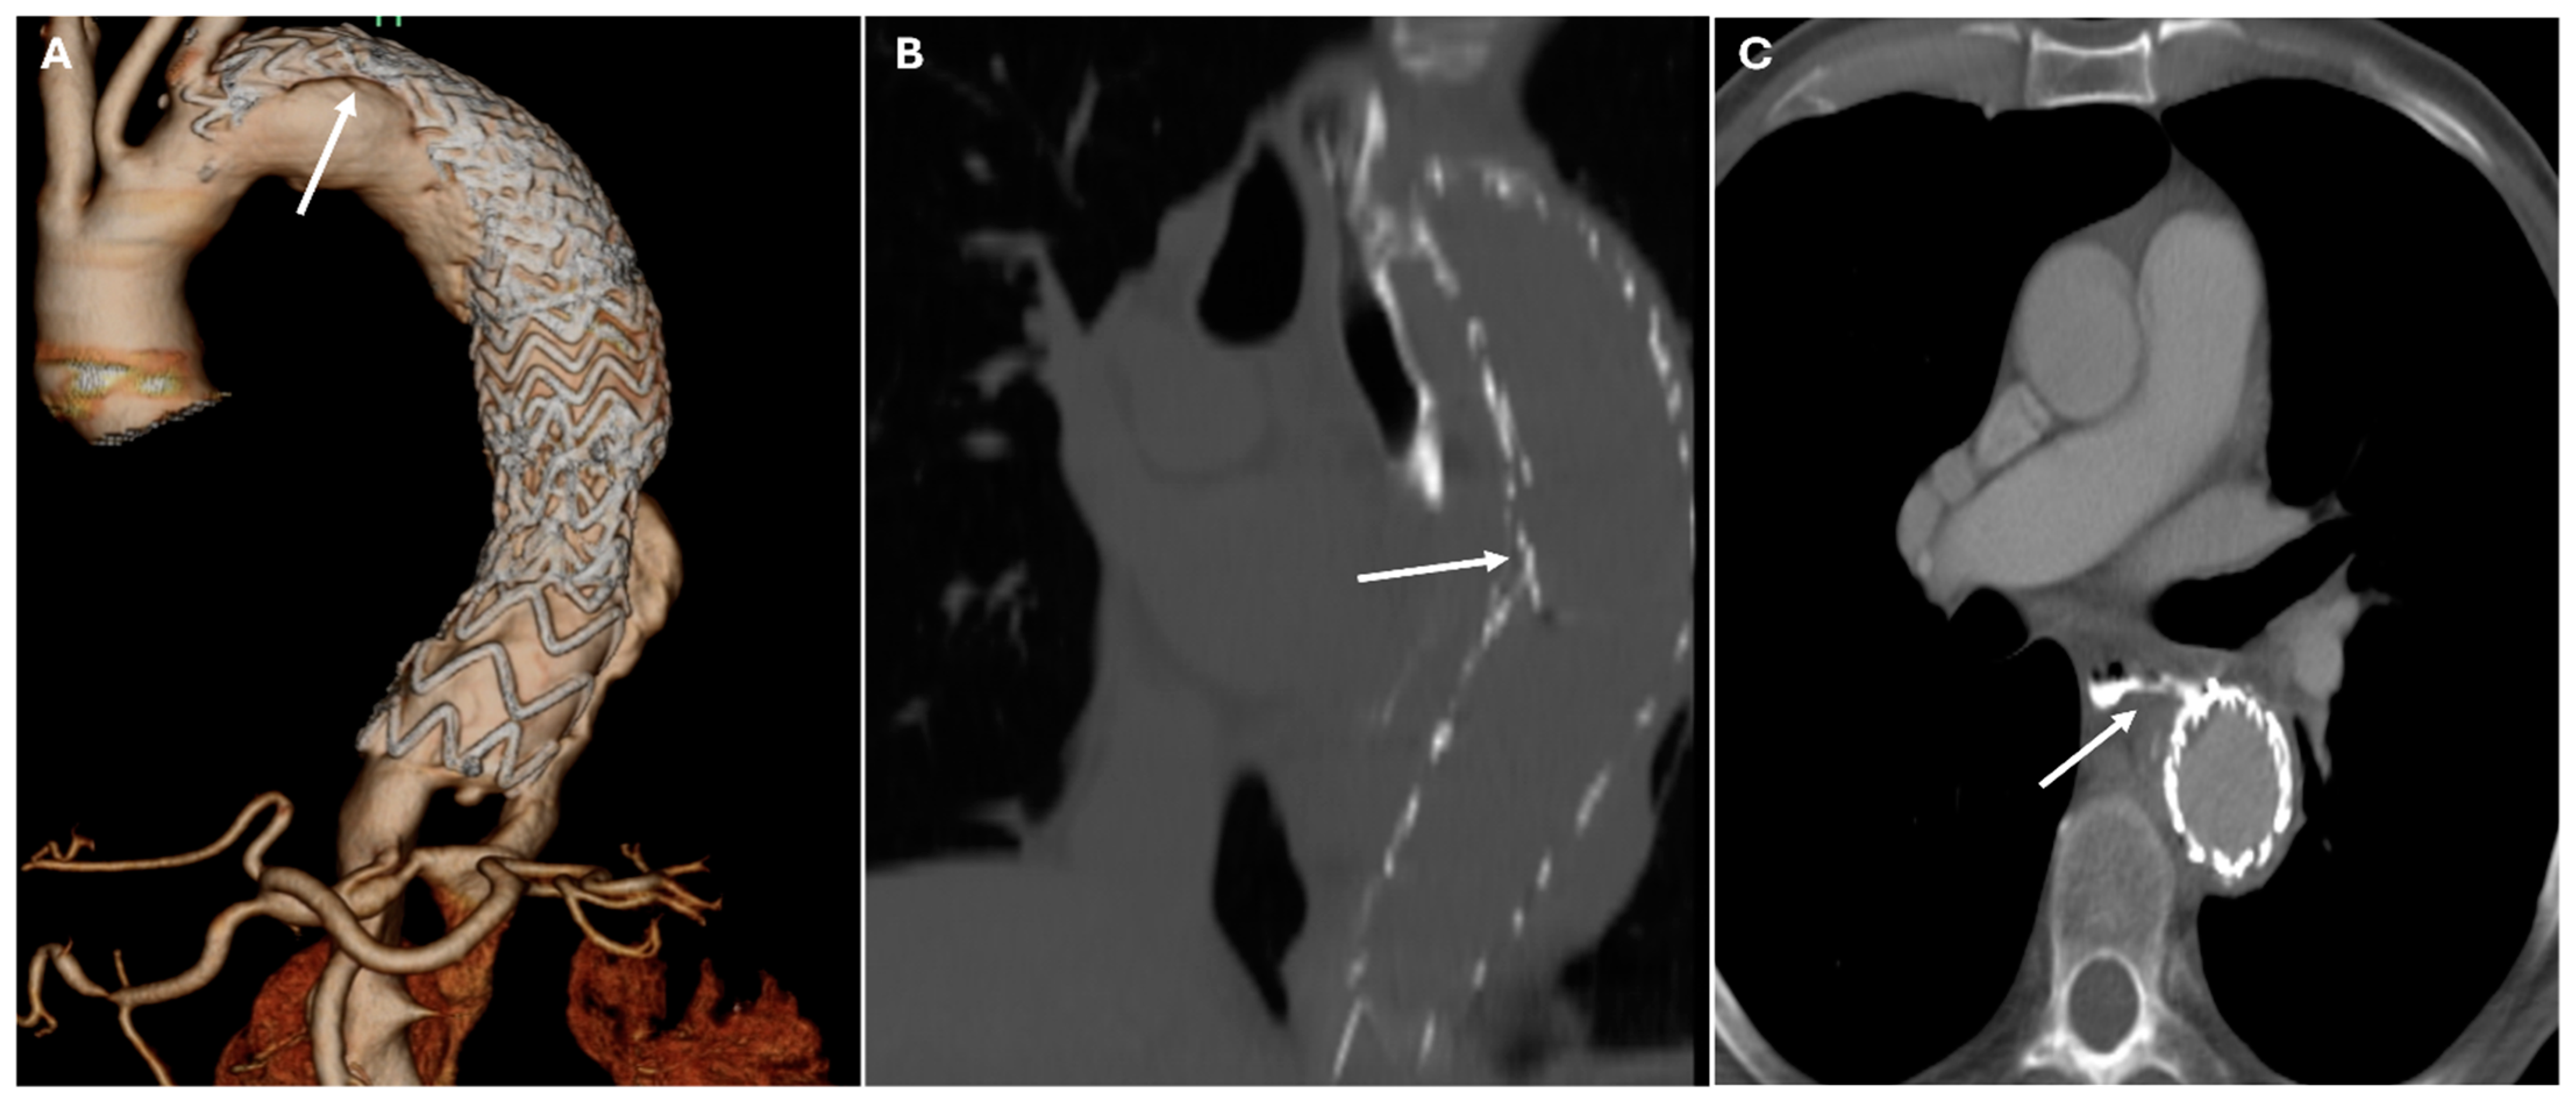

| Frozen Elephant Trunk | Single-stage aortic arch + descending repair | Endovascular stent incorporated within open graft | Seamless transition between proximal graft and distal stent |

| TEVAR | Descending aortic aneurysms, dissections | Endovascular stent placement | High-density metallic structure conforming to aortic lumen |